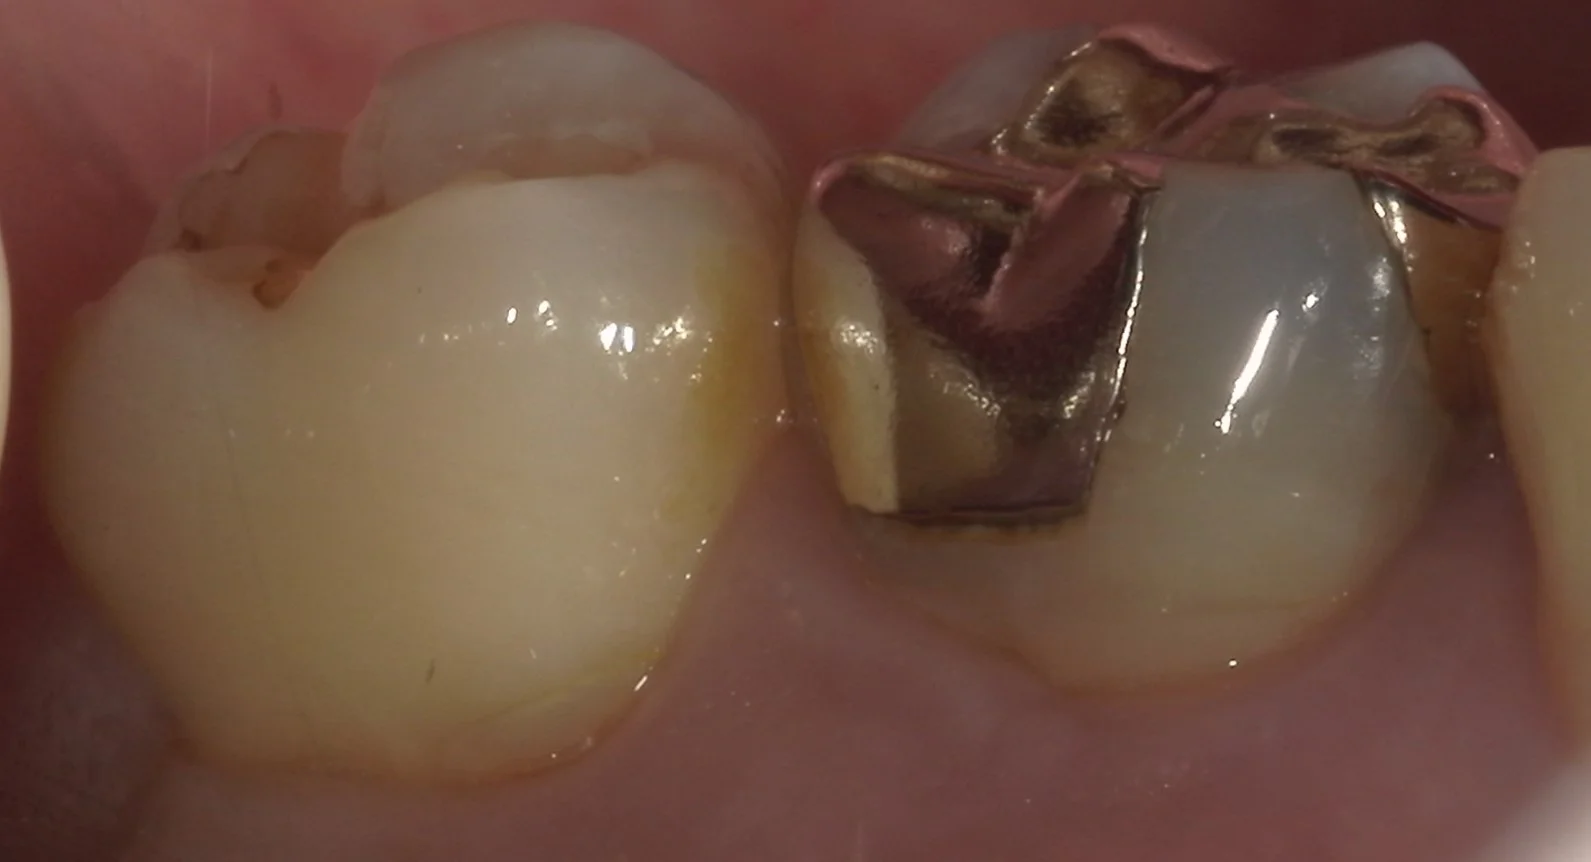

続いて、側面からの写真です。

非常に広範囲に金属の詰め物が詰められているのが分かるかと思います。

また、歯茎の際辺りが歯ブラシの圧で抉れてしまっています。

こういった状態を「楔状欠損」と言い、実はダイレクトボンディングの中で治療が最も難しいと言われている状態になります。